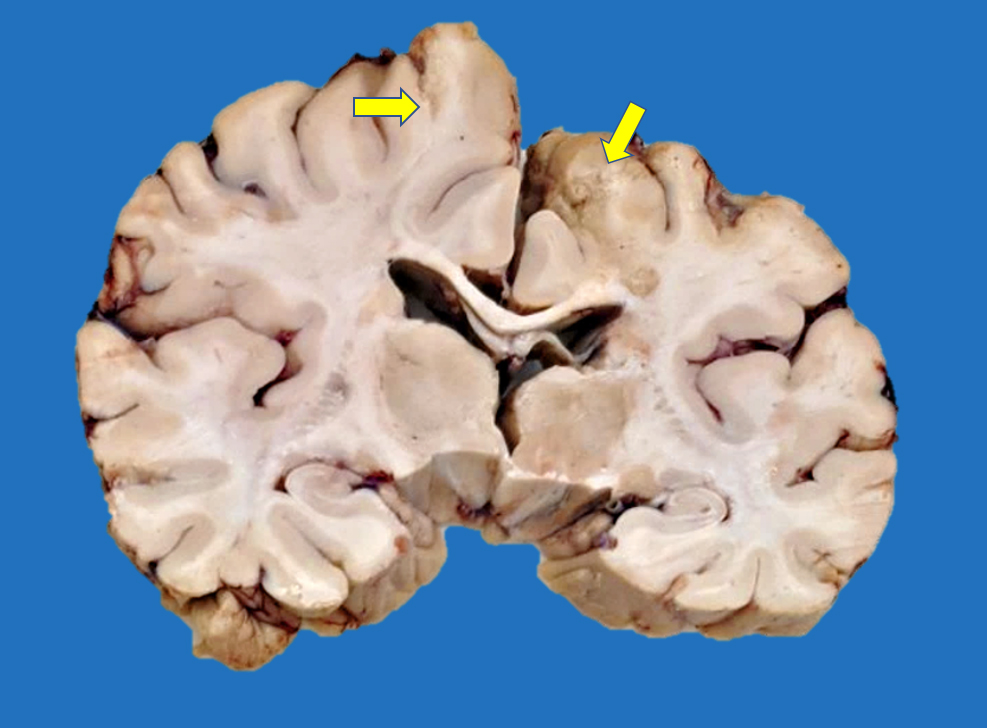

Gross description

- Time between stroke and death is a major determinant of the gross features

- Completely accurate dating of an infarct based on the gross features is not possible, especially cavitated lesions

- < 8 hours to 48 hours

- Undetectable if the infarct occurred < 8 hours before death

- Congestion of gray matter and edema (Histopathology 2011;58:333)

- Dusky discoloration and blurring of the gray-white matter junction

- Ill demarcated borders

- 2 days to a few months (Histopathology 2011;58:333)

- Marked tissue softening

- Cracking artifact: demarcates the necrotic area

- Tissue edema (e.g., midline shift, narrowing of the sulci, convexity flattening)

- Dusky discoloration and blurring of gray-white matter junction

- Chronic (months - years)

- Cavitation (i.e., cystic infarct)

- Thin cortical remnant overlying the cavitation

- In long term survivors of severe global hypoxic ischemic encephalopathy, a markedly thin cortex can be observed due to laminar necrosis

- Lateral ventricle asymmetry can be seen (i.e., ex vacuo ventricular dilation of the affected hemisphere)